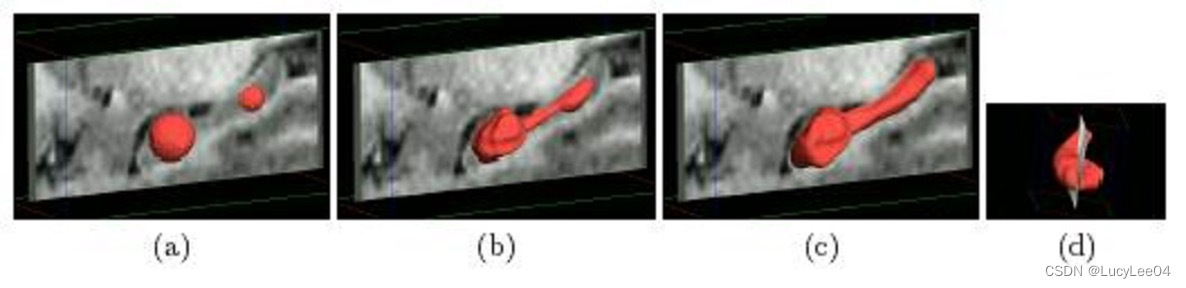

感兴趣区域的分割